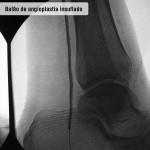

Doença obstrutiva em diabéticos